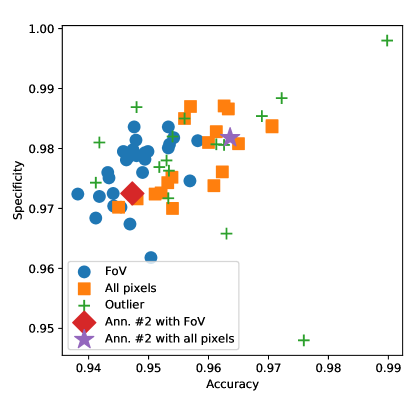

The results are summarized in Table 2 and plotted in Figure 3 in the accuracy-specificity plane. Surprisingly, 20 out of the 36 papers with image level scores turned out to be outliers. The ranking in Table 2 shows that almost all papers where the use of all pixels was accepted outperform those evaluating under the FoV mask, clearly showing the expected skew in the evaluations. A similar pattern can be seen in Figure 3: the scores where the use of the FoV mask was accepted tend to have lower accuracy and specificity scores than those where the use of all pixels was confirmed.

In some papers (such as (Wu et al., 2020)), multiple triplets of aggregated scores are reported to illustrate the effects of the various steps of the proposed methods. Similarly to the image level analysis, the majority rule is applied to make clear decisions about the region of evaluation used by the authors. The results are summarized in Table 3 and plotted in Figure 5. Again, we assigned 3 labels to the papers, in 30 cases the use of the FoV was accepted, in 18 cases the use of all pixels was accepted, and 16 papers were classified as outliers (the scores do not pass the test with either of the hypothesised regions). As before, the ranking in Table 3 and the illustration in Figure 5 confirm the expected bias in the evaluations: the algorithms evaluated on all pixels tend to have higher accuracy and specificity scores, in general.